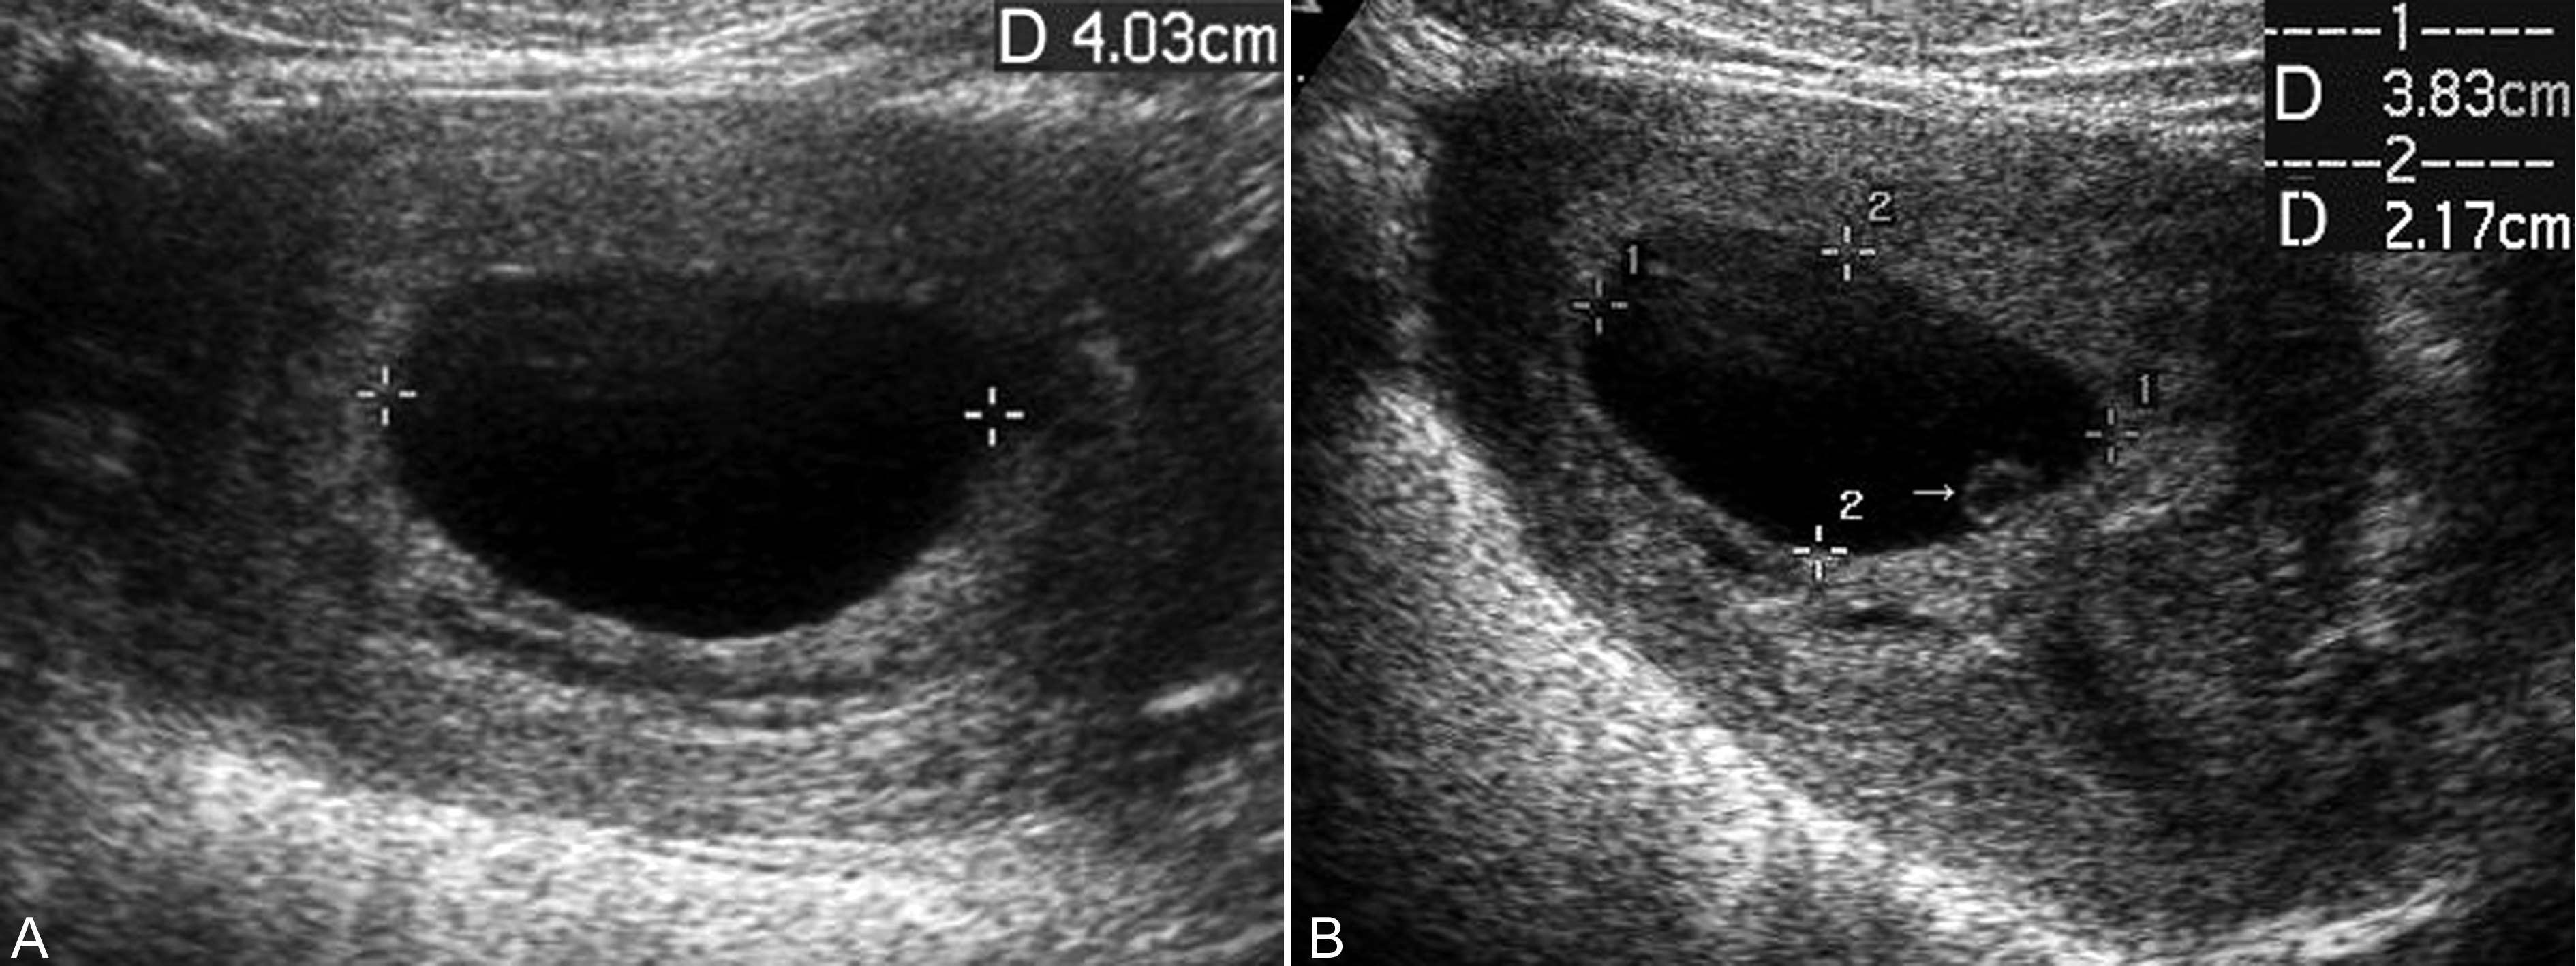

子宫及其内部的妊娠囊小于停经月份,发生早期子宫大小可能无明显变化,孕囊大小、位置和形态可以显示正常,但子宫蜕膜反应多较轻;病程较长时可以发现孕囊变形或皱缩,内部无胚胎回声。一般认为,经阴道超声检查妊娠囊平均内径25mm无胚胎显示、或显示妊娠囊两周后复查不能显示胚胎回声、或可显示胚胎回声,但无心脏活动时均提示孕卵枯萎、胚胎早期死亡(图7)。正常发育的胚胎心脏活动几乎与胚胎同时显示,当胚胎>5mm时仍无原始心脏的搏动,即可认为孕卵枯萎、胚胎早期死亡。

图7 孕卵枯萎声象图:孕囊内未见胚胎显示